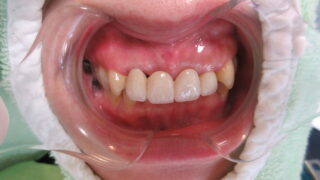

ノンクラスプデンチャー

ブリッジもインプラントも希望されない患者様にノンクラスプデンチャーを装着。薄く目立たないのが最高です。夜は享楽で食事して帰宅。